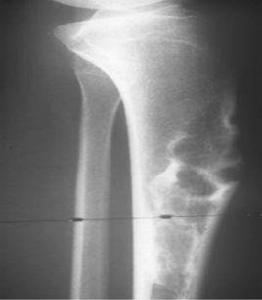

有關骨纖維結構不良的X線平片診斷已積累了相當豐富的經驗,國內文獻亦多有報導,通常將其分為磨玻璃狀、囊狀、絲瓜筋狀和蟲蝕狀,發生於頭部者則以磨玻璃狀、囊狀和硬化型多見。而有關骨纖維結構不良MRI診斷的文獻尚不多見。

在骨纖維結構不良中較常見,尤以股骨頸多見。囊狀骨纖維結構不良在X線平片表現的基礎是邊緣反應性的硬化緣,因中央的纖維成分和周圍正常的骨結構密度差異較小。但少數病灶邊緣可無硬化。